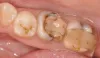

Глубокая кариозная полость в дистальном участке. Сложность в восстановлении таких полостей является в затруднённости добиться хорошей изоляции.

1 посещение: препарирование зуба 26, обработка рондофлекс оксид алюминия 27 микрон, optibond fl, восстановление стенок и основного объема реставрации.

2 посещение: препарирование зуба 27, пескоструйная обработка оксидов алюминия зубов 26, 27. Optibond fl. Реставрация зубов harmonize dentin a3, enamel a2, kolor plus ochra.

Полировка: air flow, optidisc, enhance, opti1step, occlubrush, коза.